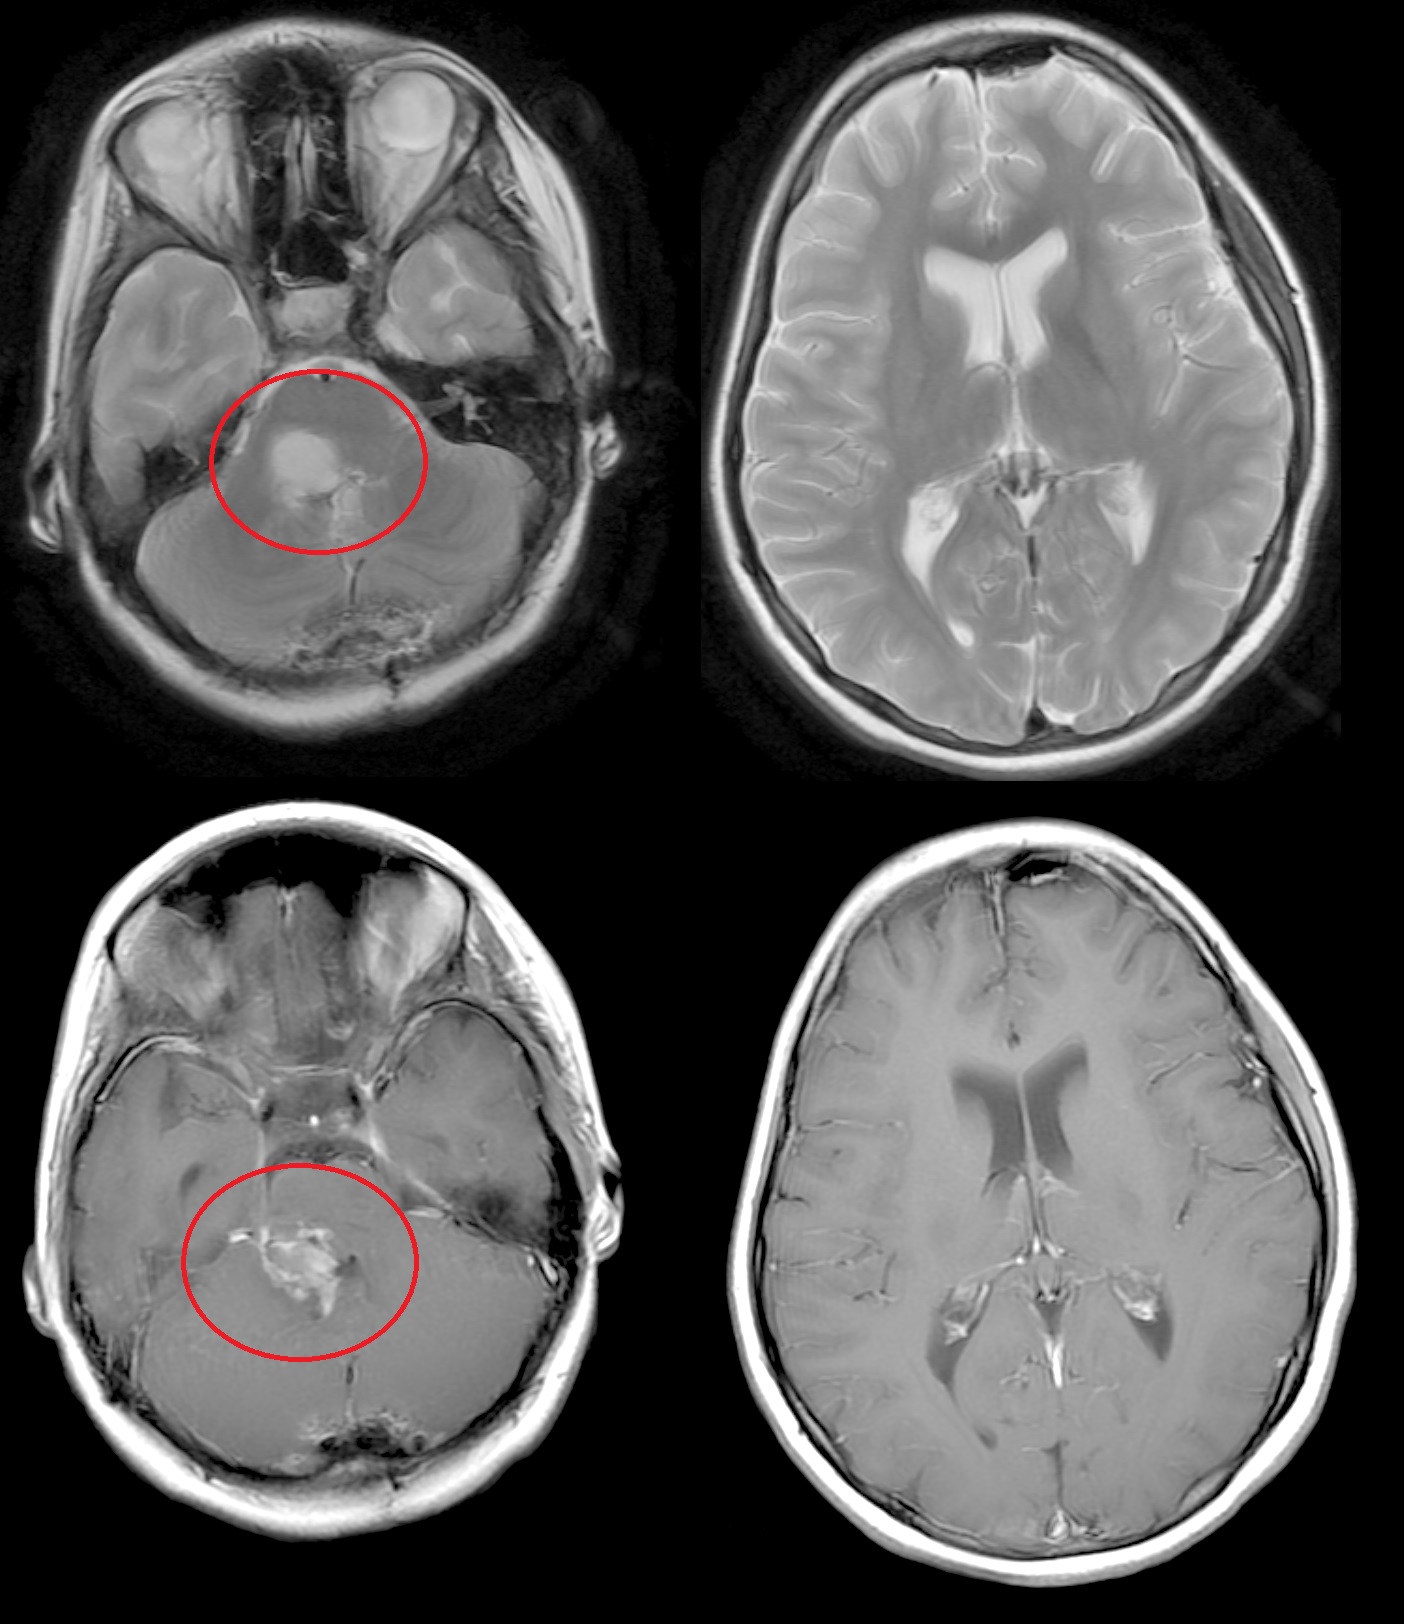

Результаты. У 19 пациентов (50 % от 38 прошедших биопсию) по данным иммуногистохимического анализа послеоперационного материала была выявлена мутация К27М в гене H3F3A. У 6 (15 %) пациентов из 38 МРТ в сроки от 2 до 5 мес (медиана – 4,5 мес) после окончания лучевой терапии выявлено нехарактерное прогрессирование ДСГ в виде метастазирования по желудочковой системе головного мозга. У остальных пациентов когорты исследования, не проходивших процедуру биопсии, подобный характер прогрессирования не наблюдался (p<0,002): у них, как правило, отмечался продолженный рост опухоли (n=96), у 4 больных диагностировано лептоменингеальное метастазирование по спинному мозгу.

Заключение. Нами выявлены случаи нетипичного прогрессирования ДСГ в виде метастазирования по желудочковой системе у детей после открытой биопсии опухоли. Есть основания полагать, что биопсия могла способствовать диссеминации ДСГ по ликворным пространствам. Необходим поиск альтернативных методов оценки молекулярно-генетических характеристик ДСГ.